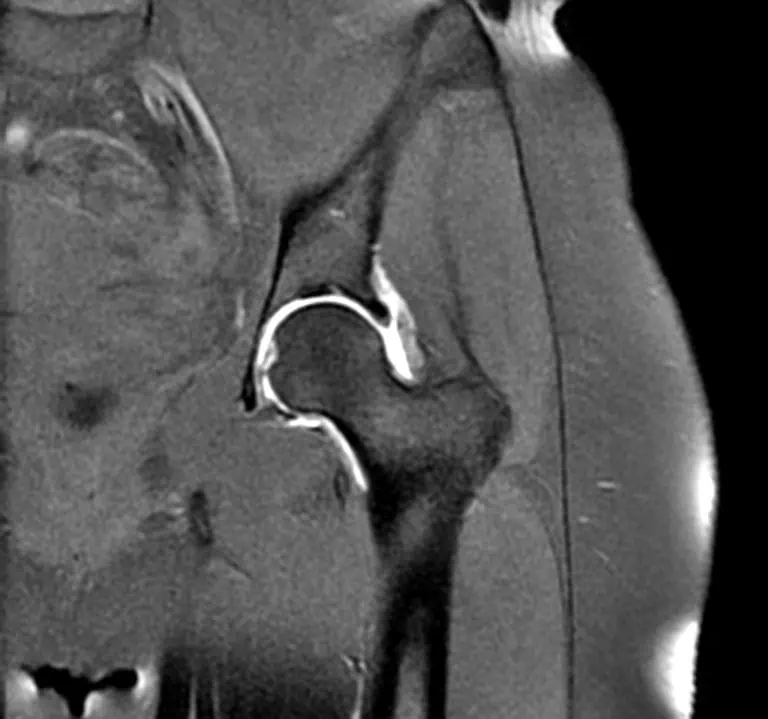

Es un estudio especializado de resonancia magnética donde el medio de contraste en vez de ser inyectado por vía intravenosa se inyecta directamente en la articulación para una mejor visualización de las estructuras articulares y mayor precisión diagnóstica en casos especiales, a estos estudios se les llama Artro-resonancia magnética y se utiliza principalmente en el estudio de la articulación de la cadera y articulación del hombro.